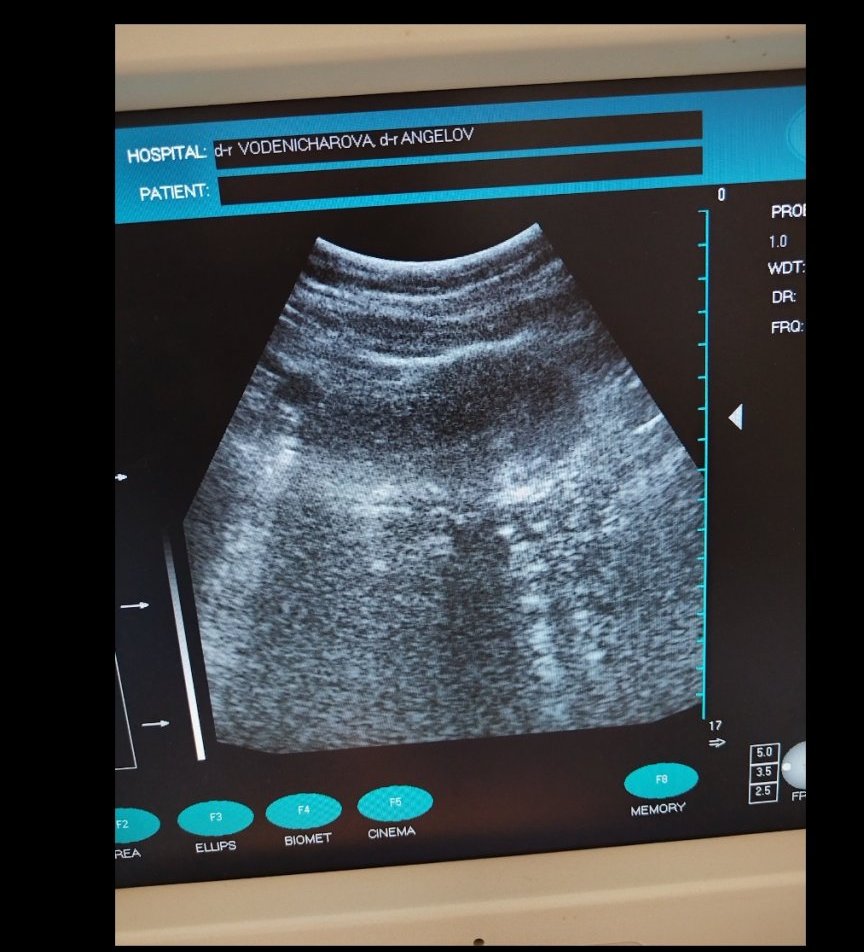

Извънматкова бременност възниква, когато оплоденото яйце се имплантира извън матката, обикновено в една от фалопиевите тръби. Симптомите могат да включват едностранна коремна болка, вагинално кървене и дискомфорт по време на уриниране или дефекация. При извънматкова бременност нивата на ЧХГ може да не се повишат както обикновено или дори да намалеят. Това е сериозно състояние, което изисква незабавно медицинско внимание, така че е важно да се консултират с лекар при съмнение за извънматкова бременност. Извънматковата бременност е състоянние, при което оплоденото яйцеклетка се имплантира извън матката, обикновено в една от фалопиевите тръби. Симптомите включват коремна болка, кървене и нерведен менструален цикъл. Това е спешно медицинско състояние, което изисква незабавно лечение. Извънматковата бременност е състоянние, при което оплоденото яйце се имплантира извън матката, обикновено в една от фалопиевите тръби. Симптомите включват коремна болка, вагинално кървене и нисък ЧХГ може да бъде показателен за това състояние. Това може да доведе до тежки медицински усложнения и изисква спешно лечение. Симптомите включват коремна болка, вагинално кървене и нива на ЧХГ под очакваните за дадената седмица на бременността.